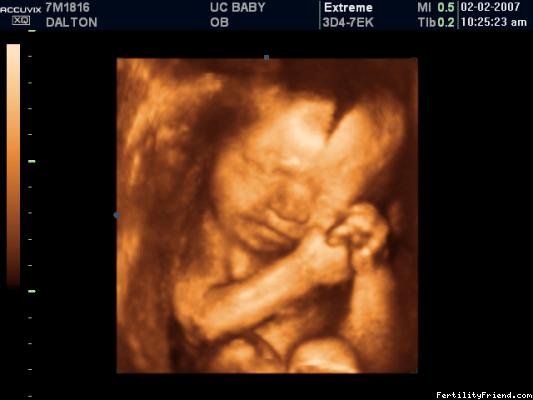

Obrázky z 3D ultrazvuku - 27. týden těhotenství

Obrázky z 3D ultrazvuku - 28. týden těhotenství